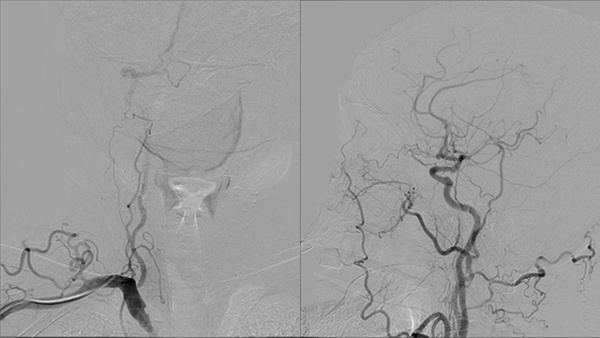

One&Done technique with optiMAX large volume coil

Stent assisted coilingAneurysms